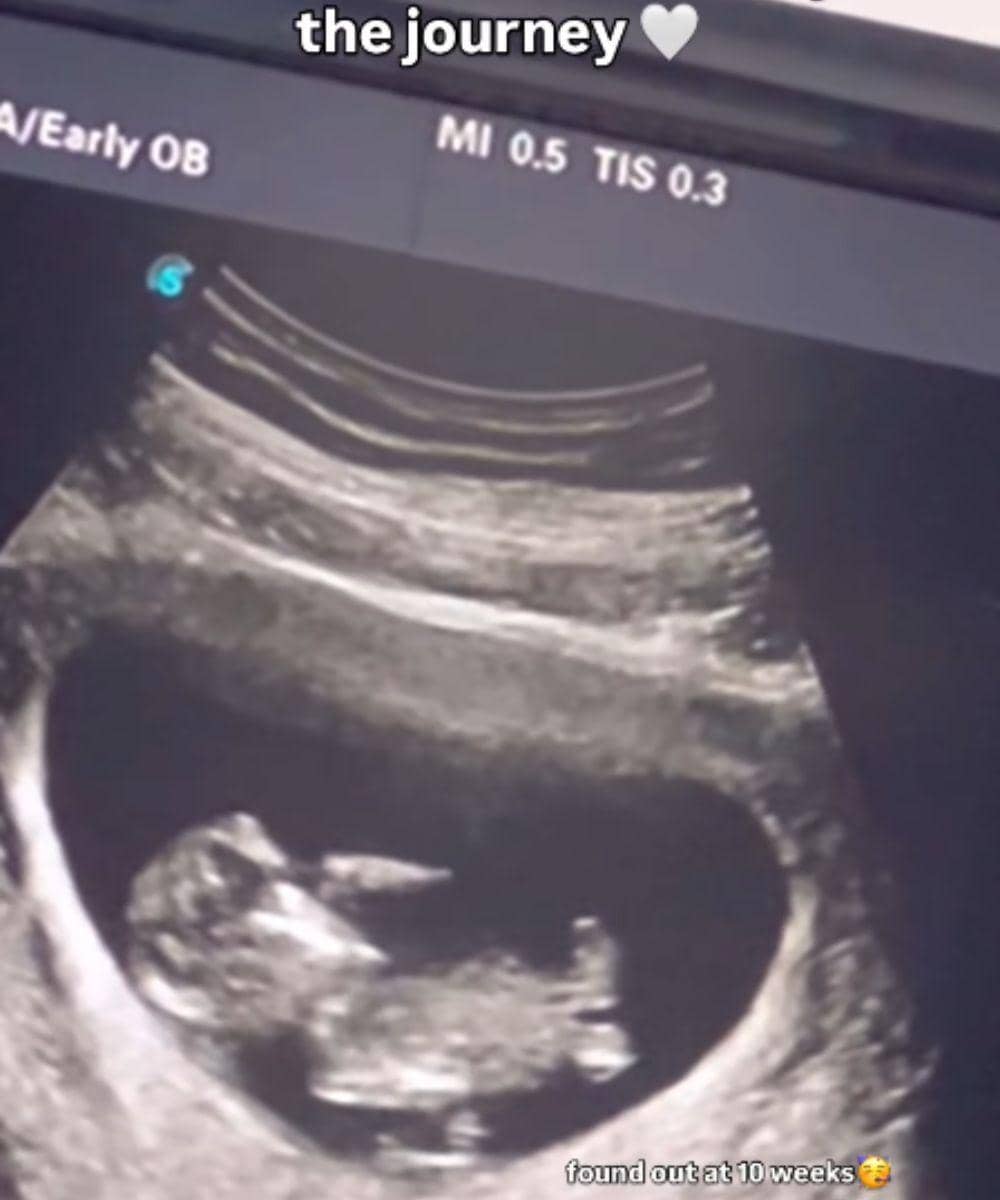

2. Kinal baru mengetahui kehamilan keduanya di usia 10 minggu

Setelah hasil test pack menyatakan bahwa dirinya positif hamil, Kinal segera melakukan pemeriksaan ke dokter. Mengejutkan, ternyata usia kandungan Kinal saat itu sudah menginjak 10 minggu, atau mulai memasuki bulan ketiga.